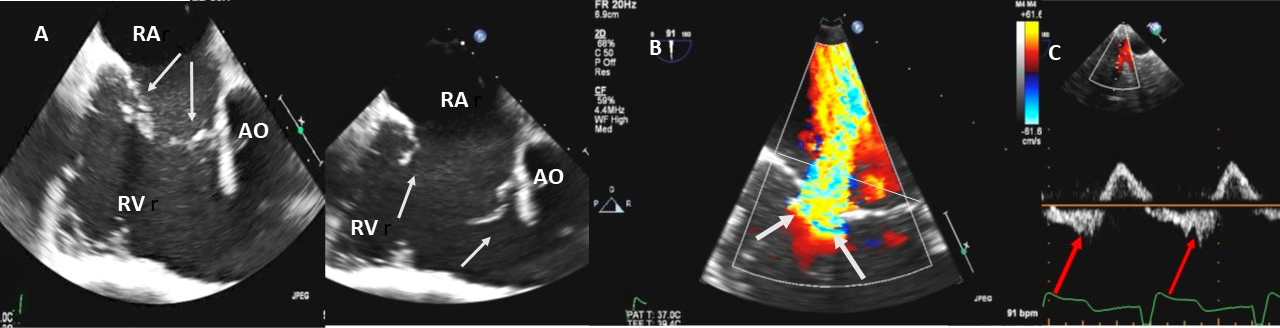

In adults TR is most commonly secondary (or functional), with normal leaflets and chords. Dilatation of the right atrium and RV with dilation of the tricuspid annulus is the most cause of secondary TR [32] (Fig. 4A–C). In an echocardiographic review of patients without primary tricuspid valve disease [33], severe TR was associated with higher pulmonary artery systolic pressure (PASP), atrial fibrillation, right atrial and RV enlargement, LV dysfunction, and primary mitral valve disease. In patients with concomitant mitral valve disease, TR is referred to as functional and is considered to be caused by filling pressure elevation in left heart, resulting in eventually tricuspid annular dilation and the tethering of tricuspid leaflets induced by RV enlargement [34, 35, 36]. This may also be true in patients with late TR after left side valve surgery [37]. Secondary TR in patients with right ventricular pressure and/or volume overload is caused by annular dilatation and increased tricuspid leaflet tethering [2].

Fig. 4.Functional Tricuspid regurgitation. (A) TEE mid esophageal inflow-outflow view shows a dilated RV and tricuspid annulus (white arrows). (B) TEE 4 chamber view color Doppler showing centrally directed severe tricuspid regurgitation with PISA (white arrows). (C) PW Doppler showing systolic hepatic flow reversal, which suggests severe TR (red arrows). RA; right atrium; RV, right ventricle; AO, aorta.

Examples of valvular injury directly from implantable cardioverter-defibrillator lead placement (Fig. 5A–C) or a permanent pacemaker (Fig. 6A–C) or endomyocardial biopsy in cardiac transplant recipients (Fig. 7A,B) are shown.

Fig. 5.Tricuspid regurgitation induced by pacemaker lead impingement. (A) 3D transthoracic echo showing and dilated RV, RA and anterior leaflet impingement by the device lead (red arrows). (B) Inspiratory systolic hepatic flow reversal (red arrows), which suggests severe TR. (C) Apical four chamber view showed severe tricuspid regurgitation. RA, right atrium; RV, right ventricle; AV, aortic valve; AL, anterior leaflet; PL, posterior leaflet; SL, septal leaflet; MV, mitral valve.

Fig. 6.Tricuspid regurgitation induced by pacemaker lead valve perforation. (A) Transthoracic 2D 4 chamber view showing pacemaker lead going through the TV leaflet (white arrow) and causing TR. (B) 3D enface view of the TV from the right atrial perspective showing the pacemaker lead going through the margin of the septal leaflet (SL) of the TV (white arrow). (C) 3D color Doppler view of the TV from the atrial perspective showing origin of TR at the site of leaflet perforation. MV, mitral valve; AV, aortic valve; PL, posterior leaflet; AL, anterior leaflet

Fig. 7.Tricuspid regurgitation following endomyocardial biopsy. (A) Flail tricuspid valve leaflet that occurred as a complication of an endomyocardial biopsy. Apical 4 chamber view showed flail septal leaflet (SL, septal leaflet; AL, anterior leaflet). (B) Color-flow Doppler imaging. Eccentric, anteriorly directed jet of tricuspid regurgitation (SL, septal leaflet of tricuspid valve; AL, anterior leaflet of tricuspid valve).